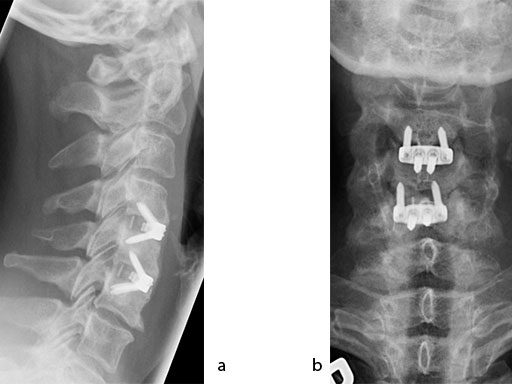

A 51-year-old woman was affected by cervical radiculo-myelopathy due to spinal and neuroforaminal stenosis. The preoperative CT scans are shown at Fig 4 and MRI at Fig 5.

The patient was treated by anterior cervical decompression and fusion (ACDF) with ZERO-P filled with ChronOS. No autologous bone graft was used. Postoperative images are shown (Fig 69).